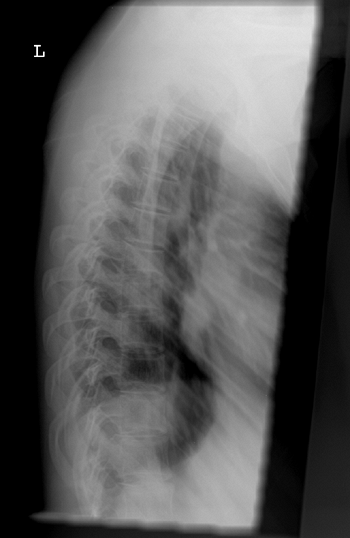

These patients have relatively large skulls but undeveloped facial

bones, leading to a characteristic triangular appearance of the face.

The sclerae of patients with type III OI are described as pale blue at

birth, but become normal in color by puberty. Patients are short, with

severe limb deformities including bowing and coxa vara (Fig. 7.9). Multiple vertebral compression fractures lead to severe scoliosis, kyphosis, and rib

cage deformity. Many patients use wheelchairs for mobility, or require

walking aids. Radiographic characteristics include very osteopenic